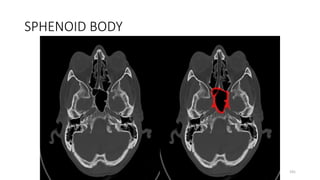

SPHENOID BONE BODY

154

SPHENOID BODY

191

BODY SPHENOID

206

217

227

237

of accessory nerve (XI)